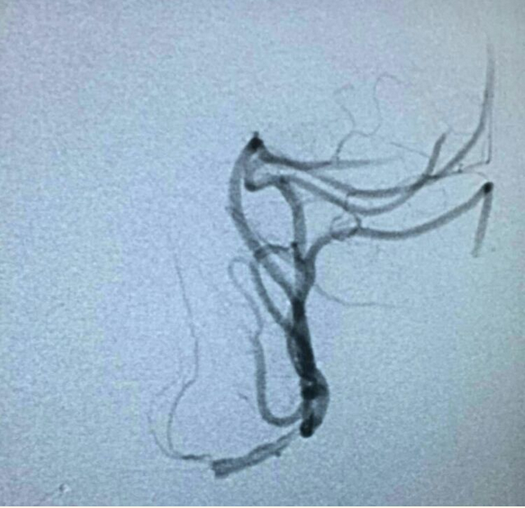

药物治疗无效症状进行性加重,拟行球囊扩张+支架成形术。微导管过狭窄后超选即见血流被完全阻断。

行球囊(gateway1.5*9)扩张: